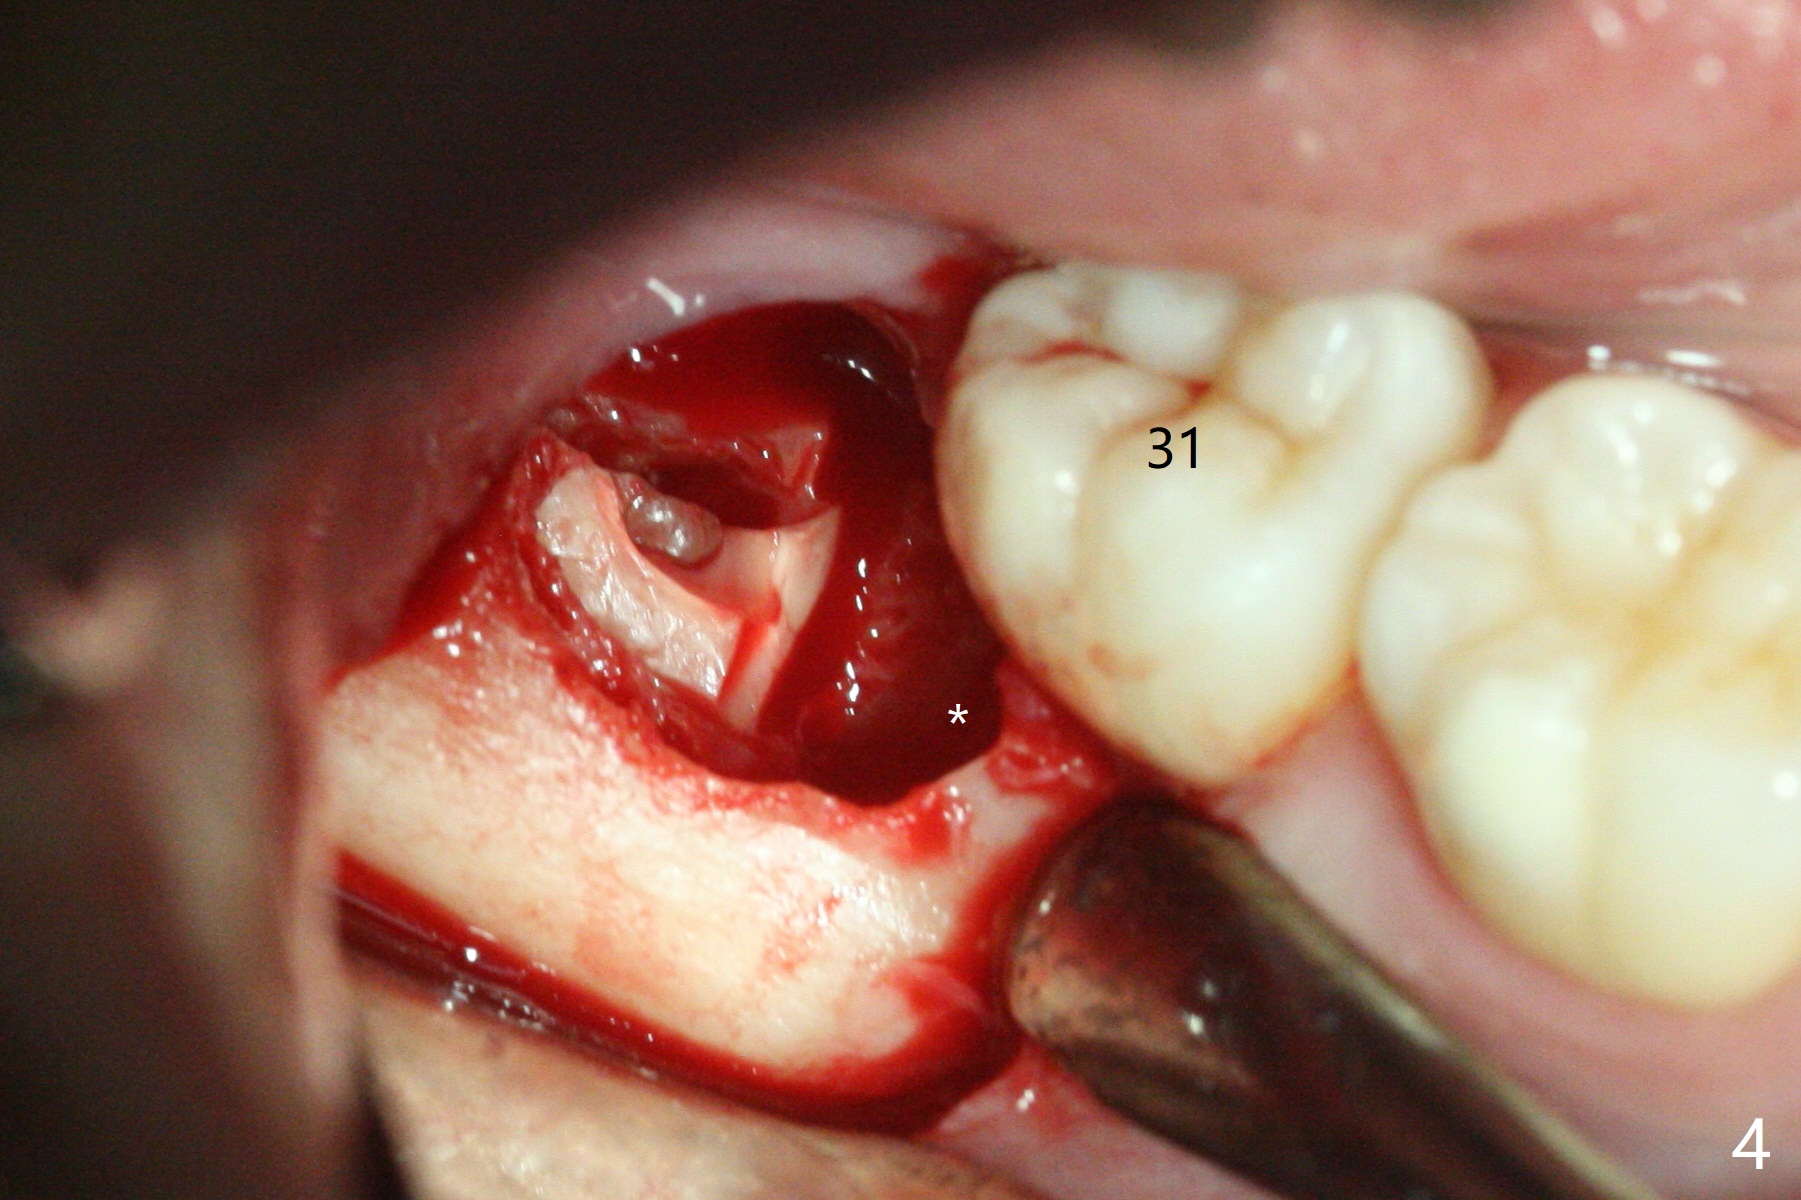

In fact the tooth #32 is extracted first; the defect involves the distobuccal aspect of the tooth #31 (Fig.4 *). An intraop PA is taken after extraction to confirm whether a broken surgical fissure bur tip retains or not; the distal lamina dura of #31 is low (Fig.5 *). It is expected to increase after cocktail bone graft (Fig.5' arrow). As planned, the bone cement (Fig.6 C) and allograft (G) are placed in the distal and mesial portions of the socket; between them is Osteogen Plug (O). Another piece of Osteogen Plug (as collagen membrane for bone graft) is placed on the top of the socket before suturing with 4-0 Plain Gut (Fig.7,7' O). Also note the bone graft being placed distobuccal (CT study) to #31 (Fig.7' red dashed line) to reduce possibility of future periodontitis. The patient returns 15 days postop with chief complaint of mild pain since extraction, although the wound looks normal. The transverse cortex connecting to the lamina dura (Fig.5 *) is obliterated when allograft is placed (Fig.7 G). The part of the graft remains in place 1 month postop (Fig.9) in spite of wound dehiscence (Fig.8). The bone graft loss is indicated by the fact of the reappearance of the transverse cortex (Fig.9). In the same appointment, the tooth #17 (Fig.10) is being extracted (Fig.11), leaving a defect mesiobuccal (Fig.12 *) to distal (curette). Part of Osteogen plug (Fig.13 O) is stretched to cover the mesially placed allograft (Fig.14 G). One quarter of Collagen plug is placed over the Osteogen plug (Fig.13 O) before 4-0 PGA suturing. There is bone regeneration 1 year postop (Fig.15,16).